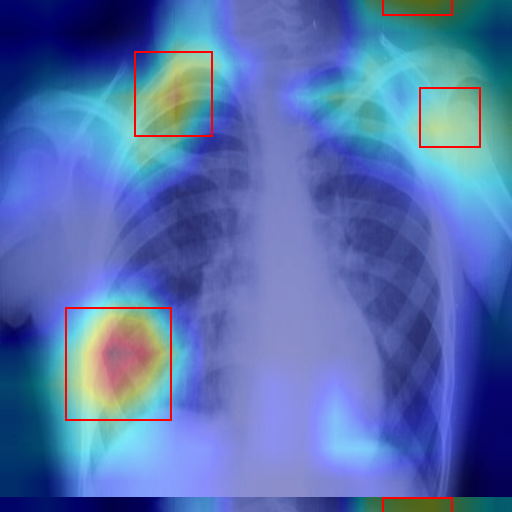

Thoracic X-Ray

Coco • Cat

2024-02-12

Pneumonia (88.7%) Completed